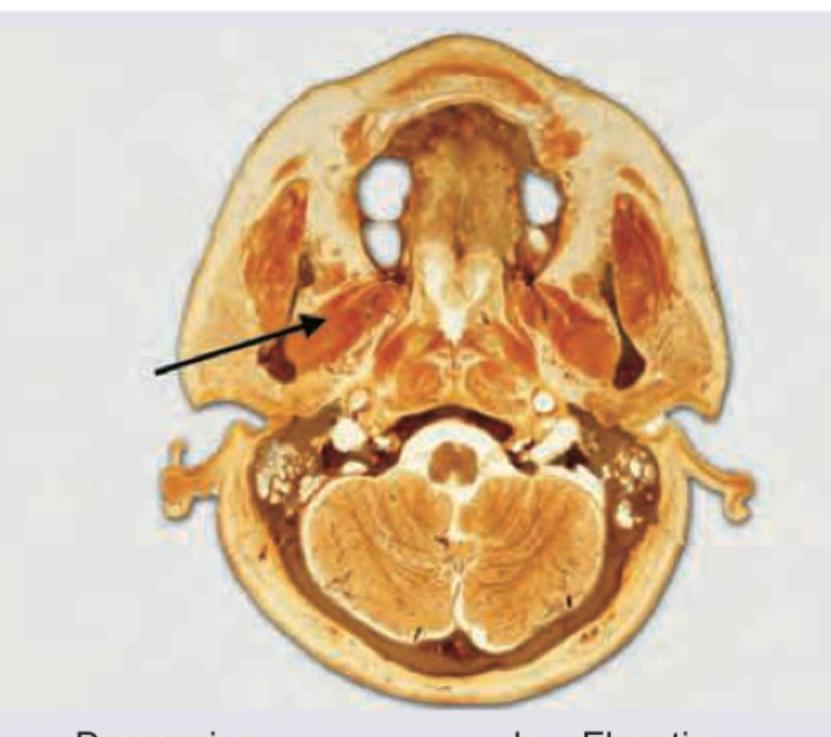

Question 58: What is the function of the muscle marked in the cut section shown below? (AIIMS May 2018)

Explanation: ***Depression*** - The image shows the **lateral pterygoid muscle** in a transverse section of the head. The **inferior head** of this muscle assists in **mandibular depression** (mouth opening) when both sides contract together. - While the **primary functions** of the lateral pterygoid are **protrusion** and **lateral excursion** of the mandible, among the given options, **depression is the only function this muscle actually performs**. - The lateral pterygoid does **NOT perform elevation or retraction**, making depression the **only anatomically correct answer** from the choices provided. *Elevation* - The lateral pterygoid muscle does **NOT elevate** the mandible - this is anatomically incorrect. - **Primary elevators** of the mandible are the **masseter**, **temporalis**, and **medial pterygoid muscles** (all supplied by the mandibular division of the trigeminal nerve). *Retraction* - The lateral pterygoid muscle does **NOT retract** the mandible - it actually **protrudes** it, which is the **opposite of retraction**. - **Mandibular retraction** is primarily performed by the **posterior fibers of the temporalis muscle** and the **deep fibers of the masseter**. *All of the above* - This option is incorrect because the lateral pterygoid does **NOT perform elevation or retraction**. - The muscle's **primary functions** are **protrusion** (forward movement) and **lateral excursion** (side-to-side movement), with **assistive role in depression** (mouth opening) when both inferior heads contract simultaneously.